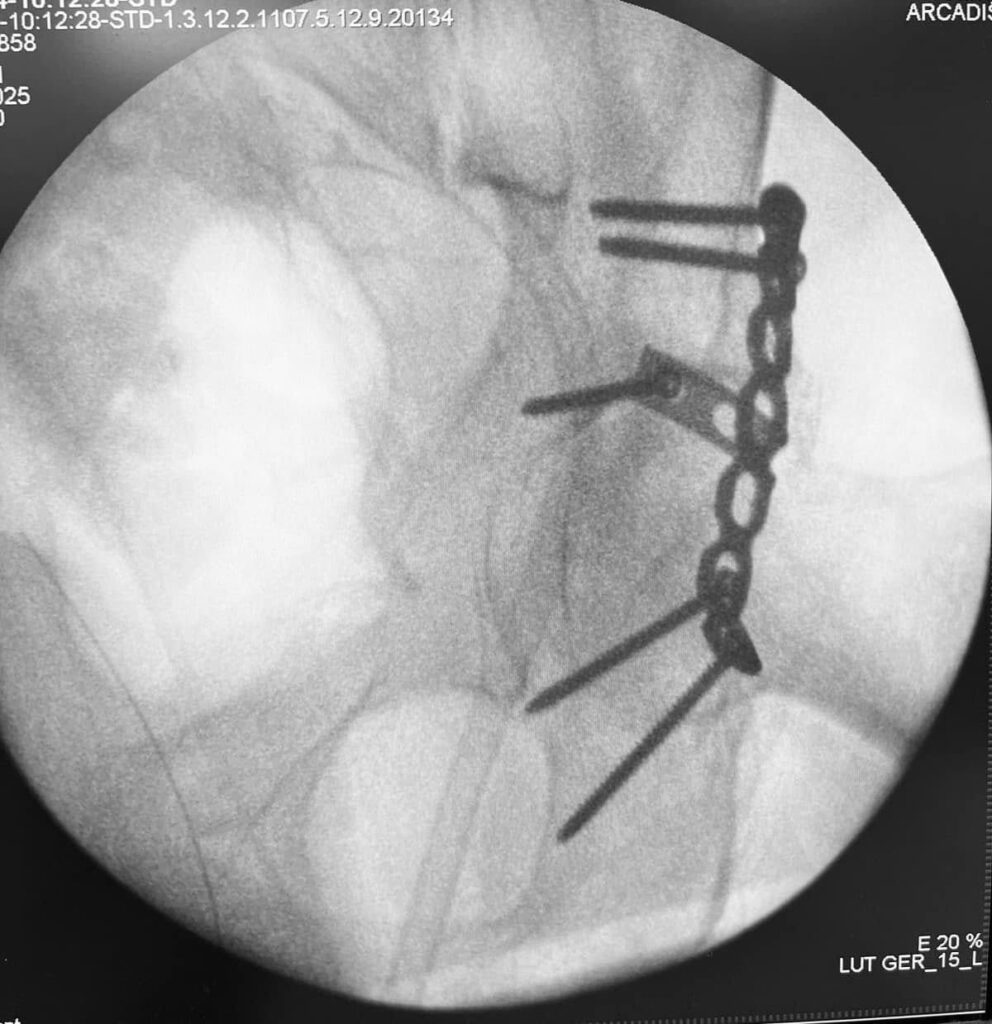

На первом фото – это заменитель кости, на втором (черно-белом, дабы Фейсбук не волновался) поверх собственной кости пациента насыпаны гранулы заменителя кости. Они блескучие такие. Недаром этот заменитель кости называют ещё и «биостекло». Потом – рентгенограмма после заключительной операции.